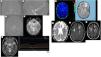

ResultsThere are 58,905 unique MRI scans from 2019 to 2023. The cohort comprises 8 females and 2 males, with a median age of 37 (7–65) years old. Three cases are probable MMD. with six MMD cases and one MMS case. Therefore, the prevalence rate for the four years is approximately 11.9 cases per 100,000 scans. Out of the confirmed Moya-Moya cases, the majority (4/7) are ischemic subtypes, followed by epileptic (electroencephalography shows slowing brain waves) and TIA in one case each. The most common presenting symptom is weakness in the extremity (N = 7), followed by headache (N = 5). Four patients underwent operative procedures, with three of them being superior temporal artery to middle cerebral artery (STA-MCA) bypass procedures and one of them being encephalo-duro-myo-arterio-pericraniosynangiosis (EDMAPS).